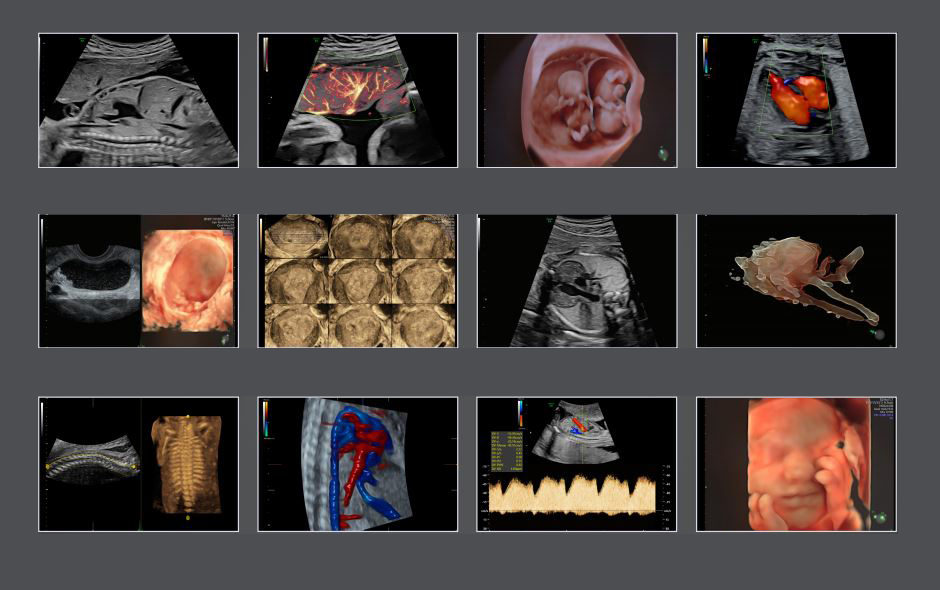

Hình ảnh siêu âm thai các tuần từ thiết bị Voluson E8

So với các dòng máy siêu âm cũ của GE thì Voluson E8 đã thiết lập tiêu chuẩn mới cho hình ảnh OB/ GYN, Radiology và 4D một cách xuất sắc, cung cấp chất lượng hình ảnh rõ nét nhất, giúp bác sĩ chẩn đoán chính xác tình hình sức khỏe của thai nhi trong quá trình siêu âm.

Bên cạnh đó, nhờ áp dụng công nghệ HDlive giúp xem các chi tiết siêu mịn, đơn giản hóa quá trình quét, tập trung chi tiết vào hình ảnh, cung cấp hình ảnh siêu âm có chiều sâu, sắc nét và chân thực nhất.

Ngoài ra, độ phân giải tương phản nâng cao với hiển thị mô, xương; mức độ chi tiết vượt trội với công nghệ đầu dò XDclear ™, Omniview đảm bảo quét được với cả những bệnh nhân khó siêu âm hay cho hình ảnh tối ưu ngay cả khi thai nhi đang chuyển động.